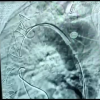

MARDİN - Torasik Aorta'nın endovasküler yöntem ile damar değişimi, tamiri olan TEVAR işlemi Mardin Eğitim ve Araştırma Hastanesi'nde ilk kez gerçekleştirildi. Gaziantep'te yaşayan 66 yaşındaki Hayrettin Şimşek, yüksek tansiyona bağlı aort damarında oluşmuş dev baloncuk şikayeti ile Mardin'e geldi. İyileşmesi için TEVAR yöntemi ile ameliyat olması gereken Şimşek'in ameliyatı sadece sayılı illerde yapılıyordu. Eski hastası olduğu Prof. Dr. Hayati Deniz ile görüşen Şimşek, ameliyat olabilmesi için Mardin Eğitim ve Araştırma Hastanesi'nde yeterli donanım ve Tıp Fakültesinde güçlü bir ekibin olduğunu öğrendi. Şimşek, Gaziantep'ten Mardin'e ameliyat olmak için geldi. Mardin Artuklu Üniversitesi Tıp Fakültesi Kalp Damar Cerrahı Öğretim Üyesi Prof. Dr. Hayati Deniz, Kardiyoloji Anabilim Dalı Öğretim Üyesi Doç. Dr. Zülküf Karahan, Anestezi Bölümü Öğretim Üyesi Doç. Dr. Hakan Akelma'dan oluşan ekiple hasta Şimşek'e TEVAR operasyonu gerçekleştirilerek kapalı yöntemle yapay damar takıldı. Kalp Damar Cerrahı uzmanı Prof. Dr. Hayati Deniz, "Hastanenin çok hazırlıklı olduğunu, daha önceden de açık kalp ameliyatları yapmaya hazırlandıklarını geldiğimde de gördüm. Ameliyathaneleri, servisleri, anjiyosu çok iyi, aynı zamanda bu sadece malzeme işi değil. Mardin Artuklu Üniversitesi'nde Dekanımız Salim Bilici Hoca'nın oluşturduğu çok kuvvetli bir ekip var. Şimdi ben tek başıma bir kalp damar cerrahı olarak hiçbir şey yapamam. Burada çok iyi anestezi doktorları var. Anestezi hocamız Hakan Akelma, aynı şekilde kardiyoloji ekibinden Zülküf hocam var. Şimdi ekip sağlam olursa sağlam işler yaparsınız. Yoksa tek başınıza dünyanın en iyi hocası olsanız da hiçbir şey yapamazsınız" dedi. "Bu işlem sayılı illerde yapılıyor" İnsanlarda aort damarının yüksek tansiyon nedeniyle balonlaşmaya başlayabildiğini aktaran Deniz, "Bu hastamızın yaklaşık 5-6 yıl önce damarında yine baloncuk vardı ve damarı yırtıldı. Biz bu hastamızı acilen ameliyata aldık ve çok ölümcül olan hastamızı yaşama tutundurduk. Sonrasında o damarların incelmesine bağlı damarları biz takip ediyoruz. Bu defa göğsün diğer arka tarafındaki damarda genişleme oldu. Biz buna balonlaşma diyoruz ve her an patlayabilecek şekilde insanlara anlatıyoruz. Ölüm riski çok yüksek olan ameliyatlar ya da bu uyguladığımız kapalı yöntem işlemler yapılıyor. Bunlar sadece Türkiye'nin sayılı illerinde başarıyla yapılıyor. İstanbul, Ankara, İzmir ve Akdeniz'de Antalya'da bunlar başarılı bir şekilde yapılıyor. Bazı illerde yapılıyor ama rutin yapılamıyor. Oralara İstanbul'dan bir ekip gidiyor, yardımcı olup tekrardan geri dönüyor. Bu ameliyatları Türkiye'nin birçok yerinde bizde de yaptık diyebilirler. Ama genelde İstanbul'dan bir ekip gelir ameliyatı yapar ve geri döner. Biz burada tamamen kendi imkanlarımızla, Artuklu Üniversitesi'nin kardiyoloji hocasıyla aynı şekilde anestezi doçentiyle kalp damar cerrahi ile Mardin Eğitim ve Araştırma Hastanesi'nin altyapısıyla dışarıdan herhangi bir destek gelmeden yapılmış bir işlemdir. Kapalı ameliyattır. Kapalı ameliyatın açık kalp ameliyatına üstünlükleri var. Bu teknoloji gerektirir. Bu teknolojide hastanemizde var" diye konuştu. Doç. Dr. Hakan Akelma, bu hastaya özel bir muamele yapılarak hastayı sedasyon ve tansiyonlarını kontrol altında tutarak, korkularını gidererek ameliyatın başarılı olması için başında durduklarını belirtti. Akelma, bu ameliyatların kapalı sistem olmasına rağmen riskli olduklarını ve mutlaka donanımlı bir ekibin ve bir anestezi ekibinin hastanın durulması gerektiğini ifade ederek başaralı işlemlerle dışarıdan gelecek vakaların artacağını söyledi. Hastanın ameliyatını kapalı anjiyografik yöntemle yaptıklarını aktaran Doç. Dr. Zülküf Karahan, "Normalde açık ameliyatla bu hastaların ölüm riski yüzde 5 ile 10'un üzerinde. Biz, kapalı yöntemle bunu yüzde 5'in, hatta yüzde 1'in altına düşürebiliyoruz. Açık ameliyat riski hastalar için daha yüksek. Çünkü uzun süre hastanede kalabiliyorlar. Enfeksiyon riski var, göğsü tekrardan açılıyor. Bu hastamız daha önceden de ameliyat olmuştu. Onun için riski biraz daha fazlaydı. Biz ekip olarak hem kalp damar cerrahi hem anestezi hem de bizim anjiyografi laboratuvarındaki personellerimizle hastamızı kapalı bir yöntemle damarına başarılı bir şekilde yapay bir damar taktık" şeklinde konuştu. Hasta Hayrettin Şimşek ise, hastanenin 4 yıldızlı otel olduğunu ve çok riskli olan ameliyatının Mardin Eğitim ve Araştırma hastanesinde gerçekleştirmek isteyip Gaziantep'ten Mardin'e geldiğini belirtti. Şimşek, ameliyatını yapan ekibe teşekkür etti.